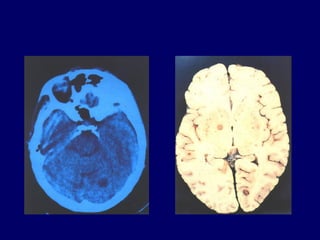

forme majeure : encéphalo-méningo-

myélite toxoplasmique

transmission :début de la grossesse :

• Des calcifications: pathognomoniques, en coup

d’ongle ou arrondies(temporal, occipital, thalamique

et ventriculaire (échographie, radiographie).

• Dilatations ventriculaires avec hypertension

intracrânienne (hydrocéphalie). Macrocéphalie

• Signes neurologiques variés